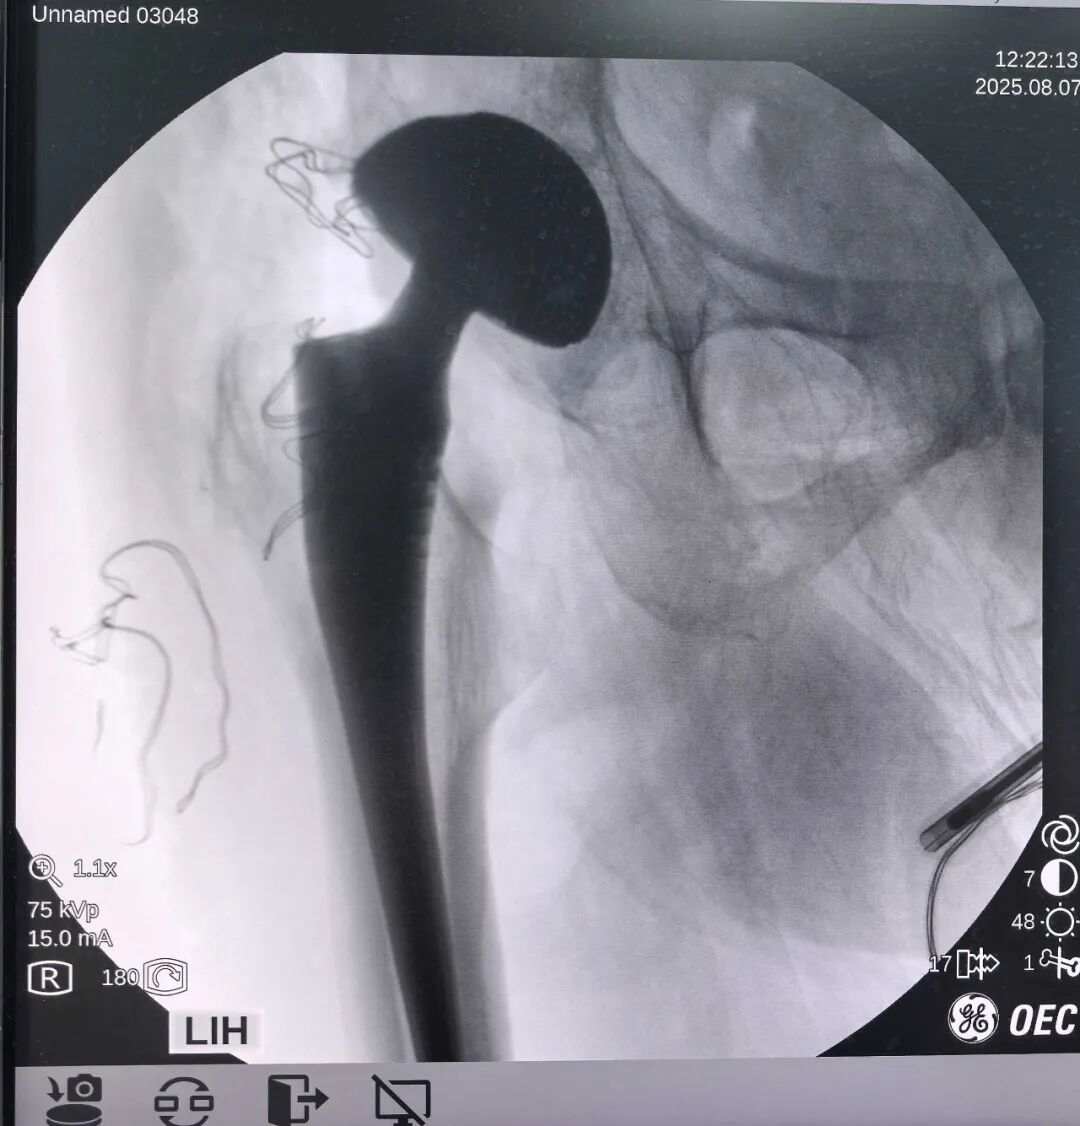

由于过程很简单,十来分钟即手术结束,故中间没有拍摄更多的照片。

磨锉过程中,松质骨突然变少,甚至出来一点点脂肪,就意味着卵圆窝到了。

前路关节置换复位过程要容易得多,同时减少了对坐骨神经的牵拉。下图复盘复位难易程度:

两种切口“复位路径”明显不同